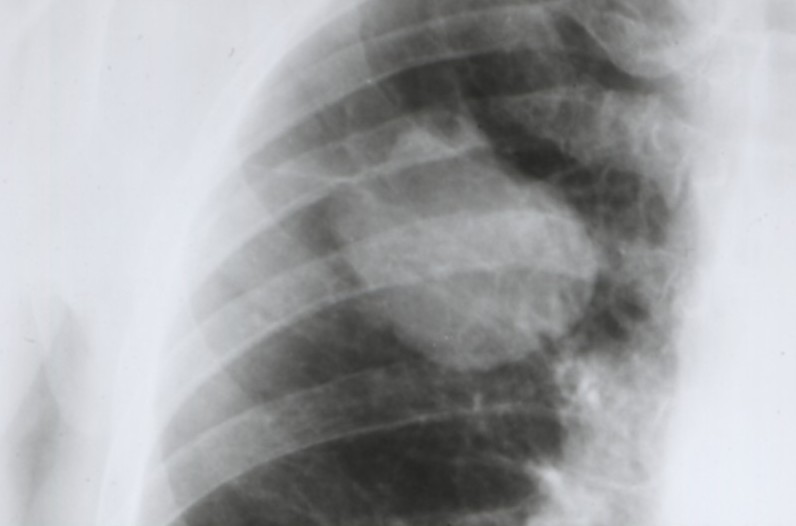

Cancers bronchiques